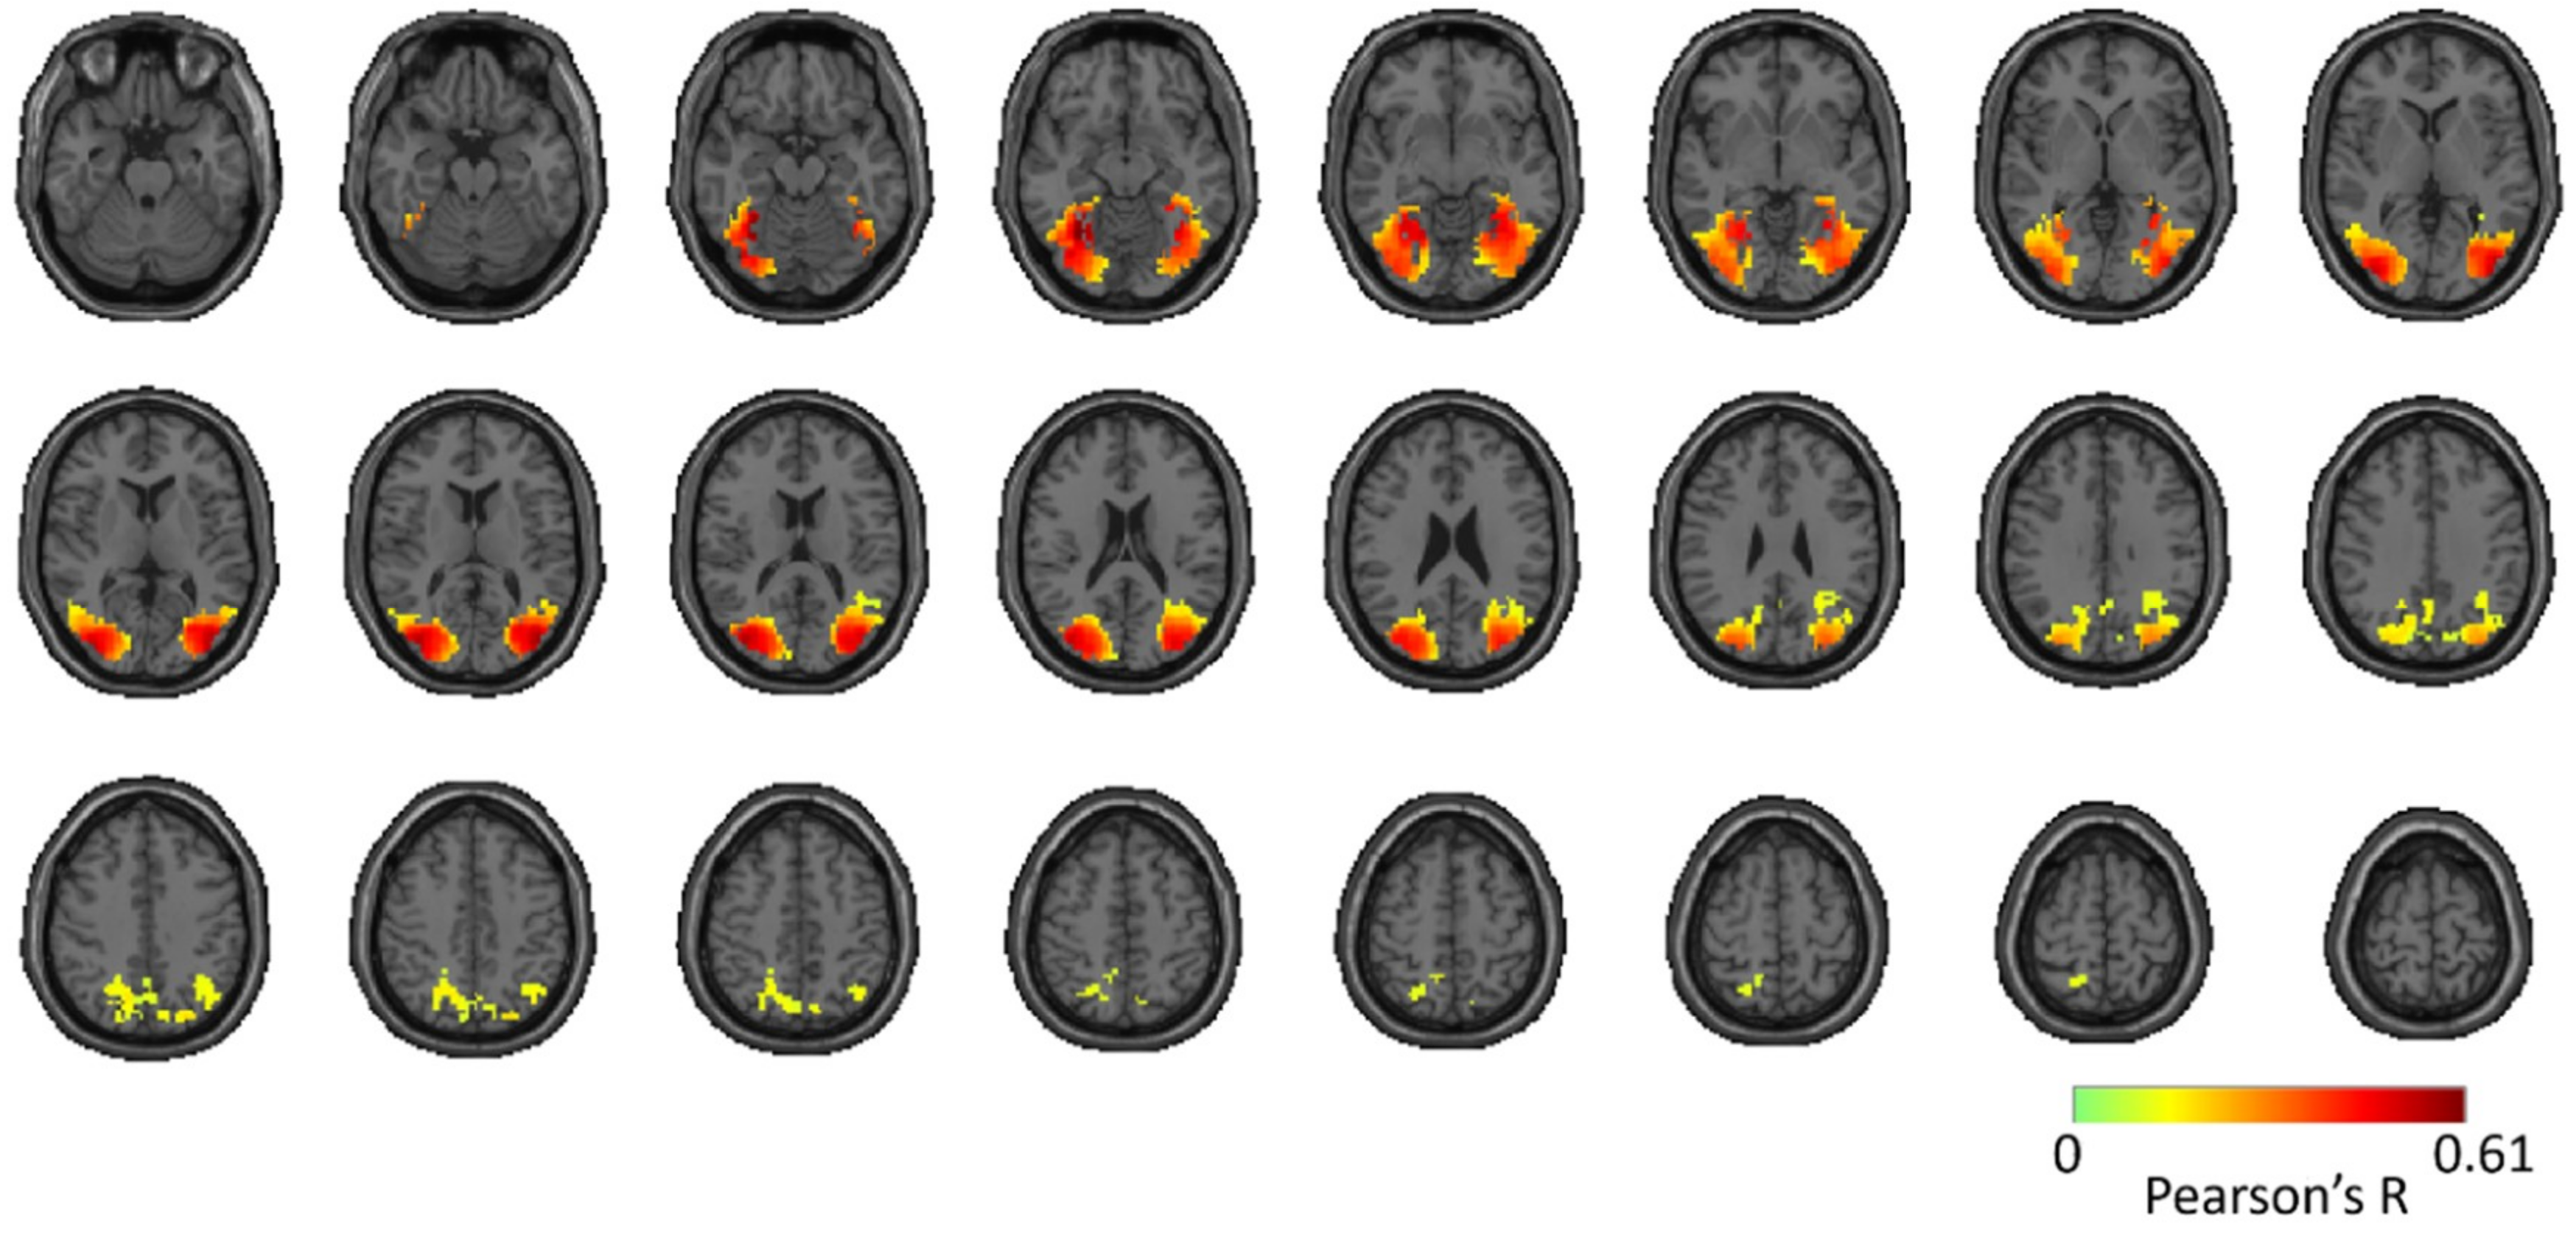

Reliability Maps